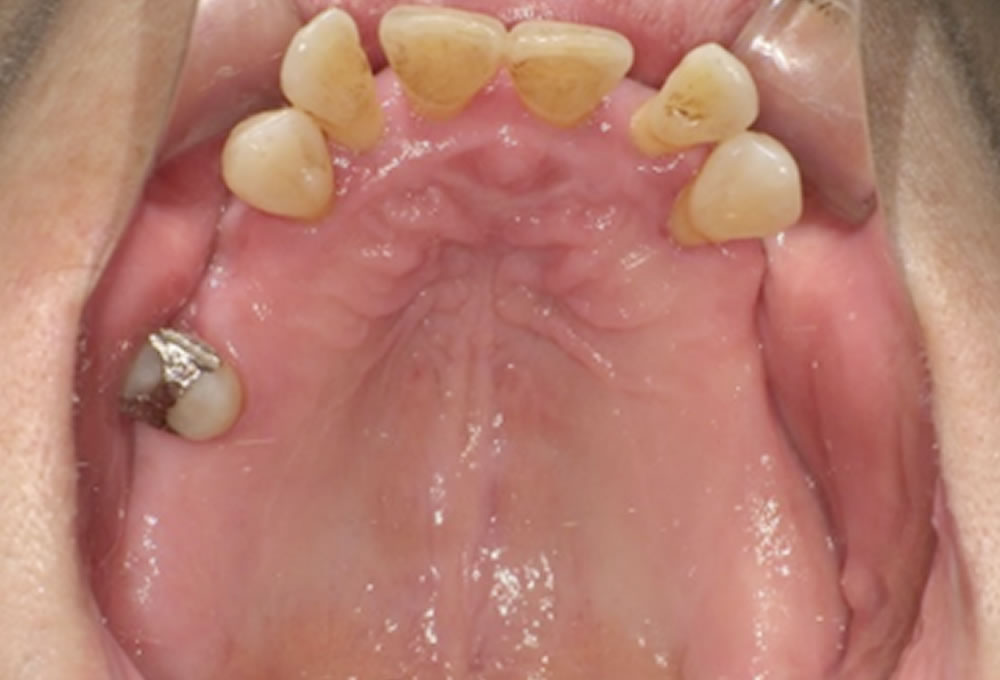

初診時の状態

奥歯から先に悪くなり欠損が進行した結果、噛み合わせのバランスが崩れ、前歯が押し出されて歯並びが乱れている状態でした。

また、1本だけ残っている歯もありましたが、周囲に支えがないため動揺があり、将来的にどこまで長持ちするか懸念される状態でした。